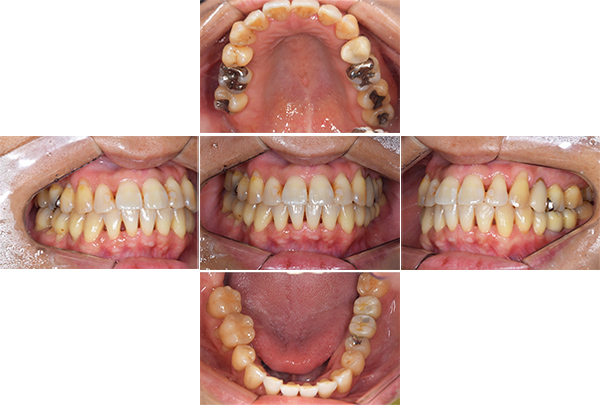

| 年齢 | 30代女性 |

|---|---|

| 主訴 | 虫歯がたくさんあり、銀歯に穴が空いているのが気になる |

| 治療期間 | 1年半 |

| 費用 | ・左下67FCZインプラント: 440,000円×2 ・右上7GBR+サージカルガイド+IV: 110,000円+55,000円+77,000円 ・右下6FCZクラウン: 110,000円 ・右下75・右上654・左上67・左下5セラミックインレー: 55,000円×8 |

※全て税込となります。

【担当医師所見】

左下奥歯は親知らずが原因でクラウン(かぶせ物)の下まで虫歯になっています。 またその手前の歯は根中央部に大きな透過像(黒い像)が見られます。クラウン除去後、マイクロスコープ下で確認したところ中央部は亀裂が入り保存不可能な状態になっており抜歯となりました。

また右上6番にも大きな透過像があり虫歯となっていることがわかります。

①親知らず手前の歯はクラウン(白い不透過像)直下に大きな透過像(黒い部分)が見られこのような場合は抜歯になる確率が高いです。

②歯根分岐部(中央部)に及ぶ歯周炎ー根尖性歯周炎の原因はクラウン除去後にマイクロスコープ下にて破折線を確認したため抜歯となりました。

右上の銀歯の下にあった虫歯は大きかったものの歯の神経を残すことがなんとかできたので部分的なセラミックのつめ物(セラミックインレー)での治療となりました。

また反対側の奥歯も古くなっており、将来性を考えセラミックへ変更しています。

右下の大臼歯部は抜歯後治癒を待ち、骨造成とインプラント埋入を同時に行いました。上部構造はFCZ(ジルコニアセラミッククラウン)となっています。

また左下の親知らずは虫歯のため抜歯、左下7番と5番はセラミックインレー、6番はFCZにて補綴しました。

※FCZ:ジルコニアより少しマイルドな硬さで審美性と機能面に優れているクラウン

全体の治療終了より1年半経過していますが、右下インプラント周囲に骨吸収の像など無く問題なく経過しています。またその他虫歯治療部位や歯の神経治療部位に関しても病変の所見は無く概ね良好と思われます。

| 治療方針 | ・歯周病治療 ・その後必要な部位の抜歯を行いインプラント治療を行う。 ・根管治療(根の治療)やう蝕(虫歯)治療を行う。 |

| 治療内容 | ・歯周基本治療:スケーリング・TBI ・下顎臼歯部:抜歯後、インプラント治療 ・その他カリエス:セラミック治療 |

| 特記事項 | 歯科恐怖症 |